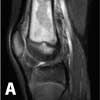

An MRI scan with gadolinium was ordered for further evaluation of the vague knee pain. It was performed using a 1.5-T magnet.

The MRI scan of the right knee revealed extensive marrow infiltration with multiple pockets of fluid in the distal femoral diaphysis and metaphysis measuring 7.4 3 1.5 3 1.5 cm. High signal was demonstrated on both T2-weighted fat-saturated and T1-weighted fat-saturated post-gadolinium sequences involving the medullary cavity and the surrounding cortex and periosteum (Figure 2). No subperiosteal fluid collection or fistulas were evident.